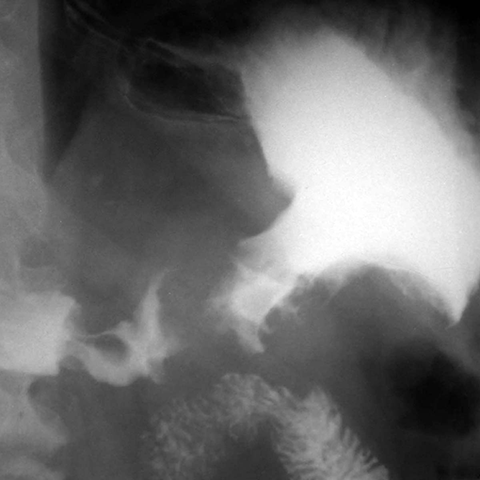

56 year-old male presents with abdominal pain and weight loss [1 of 5]